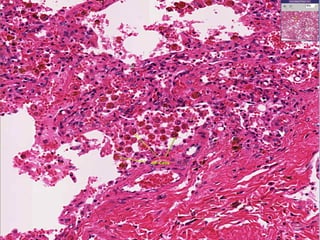

CVC Lungs Micro:- Rupture ofcongested vessel results in edema & hemorrhage. The alveolar septa appears thickened and fibrotic. The alveoli are dilated and contain edema fluid and RBC’s and macrophages. Lysis of RBC’s releases hemosiderin pigment which is taken up by macrophages in the alveoli – HEART FAILURE CELLS.

• #18 View of pulmonary congestion and edema. Often caused by an increase in hydrostatic pressure, a protein poor transudate seeps into interstitial and alveolar spaces. Note the engorged alveolar wall capillaries. If capillaries rupture, RBCs will escape into the alveolar space

• #19 Heart failure cells are hemosiderin laden macrophages. Blood escapes into the alveolar space because chronic congestion causes the thin walled alveolar capillaries to burst. Note the thickening of the alveolar septae. This is caused by chronic pulmonary congestion and edema. Note the thickening of the alveolar septae. This is caused by chronic pulmonary congestion and edema.